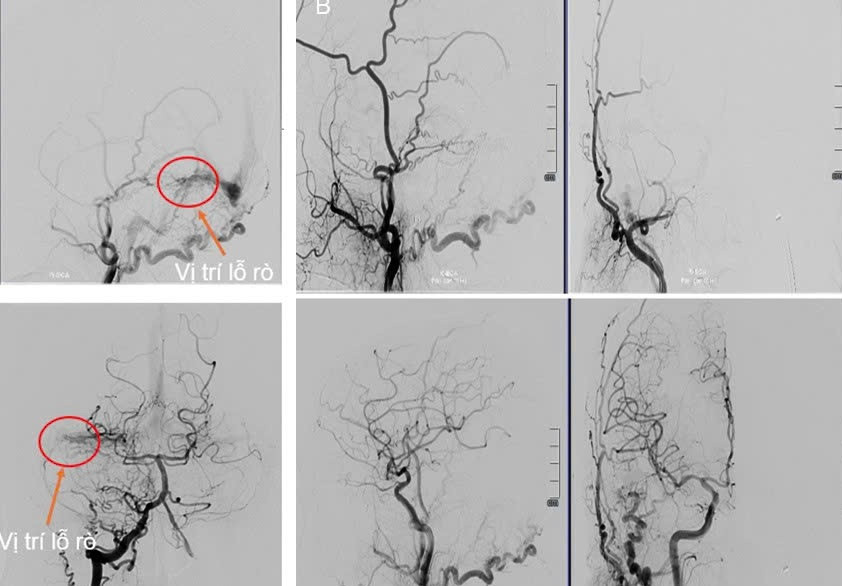

| Hình ảnh mạch máu não của người bệnh trước (ảnh bên trái) và sau khi can thiệp |

“Sau gần 2 giờ can thiệp, chúng tôi phải dùng cả hai phương án tiếp cận can thiệp đường động mạch và tĩnh mạch. Ê kíp đã thả coils và bơm keo thành công, tắc được vị trí rò. Sau 1 tuần can thiệp và theo dõi, điều trị, sức khỏe bệnh nhân đã bình phục tốt” – BS Linh nói.